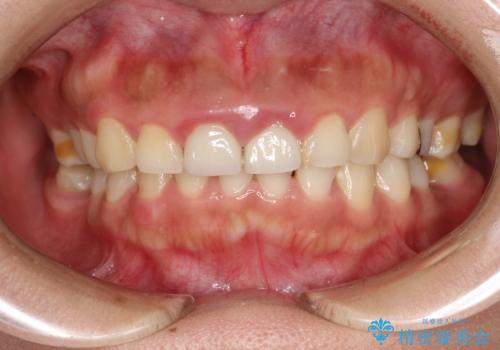

開始前

- 矯正治療のご相談で来院されました。歯科がかなり久々とのことでまずは、全体的なクリーニング希望とのことでした。